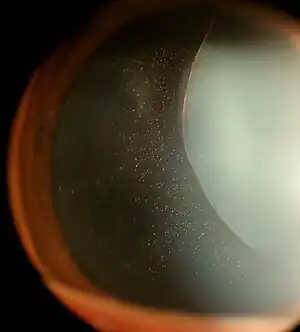

Ectopia lentis in Marfan syndrome: Zonular fibers are seen.

Lens dislocation in Marfan syndrome with the lens being kidney-shaped and resting against the ciliary body

In Marfan syndrome, the health of the eye can be affected in many ways, but the principal change is partial lens dislocation, where the lens is shifted out of its normal position.[15] This occurs because of weakness in the ciliary zonules, the connective tissue strands which suspend the lens within the eye. The mutations responsible for Marfan syndrome weaken the zonules and cause them to stretch. The inferior zonules are most frequently stretched resulting in the lens shifting upwards and outwards, but it can shift in other directions as well. Nearsightedness (myopia), and blurred vision are common due to connective tissue defects in the eye.[16] Farsightedness can also result particularly if the lens is highly subluxated. Subluxation (partial dislocation) of the lens can be detected clinically in about 60% of people with Marfan syndrome by the use of a slit-lamp biomicroscope.[16] If the lens subluxation is subtle, then imaging with high-resolution ultrasound biomicroscopy might be used.[17]